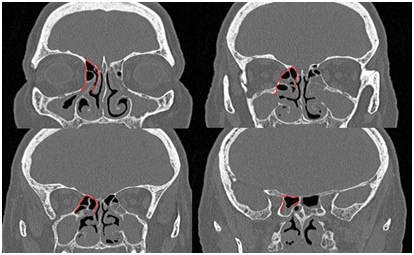

The posterior rim of the frontal ostium is chosen as the most anterior point of the ethmoidal roof accessible with a 0o endoscope as we try to complete the operation with this endoscope. After the induction of general anesthesia the operation begins. The first steps are typical of fess removing polyps and opening the ostia of the paranasal sinuses. The frontal wall of the sphenoid sinus is almost completely removed to the skull base making use among others of 15o a curved diamond DCR bur (Figure 3).

Figure 3 Removing fine bony septa by making use of the DCR bur.